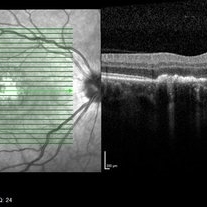

Unilateral Acute Idiopathic Maculopathy OCT Macula

A 37-year-old female presented with a two-week history of vision loss in the right eye. She experienced a flu-like illness including rash on the hands, feet, and mouth 2 days prior to her vision change. Her 3-year-old son had a similar illness diagnosed as hand, foot, and mouth disease by his pediatrician one week prior. Her visual acuity was 20/150 of the right eye, and 20/20 of the left eye. On dilated fundus examination, the left eye was unremarkable; the right eye revealed a circular, variably pigmented lesion of the macula. OCT imaging showed areas of RPE loss and clumping, with overlying loss of the photoreceptor layer. Fluorescein angiography showed central and peripheral hyperfluorescence consistent with window defect, and blockage in area of RPE loss. No treatment was initiated at this time. The patient returned 10 days later; her visual acuity improved to 20/50 in the right eye. Dilated fundus exam showed increased pigmentation of the macular lesion. OCT of the right eye showed further RPE clumping without recovery of the photoreceptor layer, despite her improved visual acuity.

Condition/keywords: unilateral acute idiopathic maculopathy